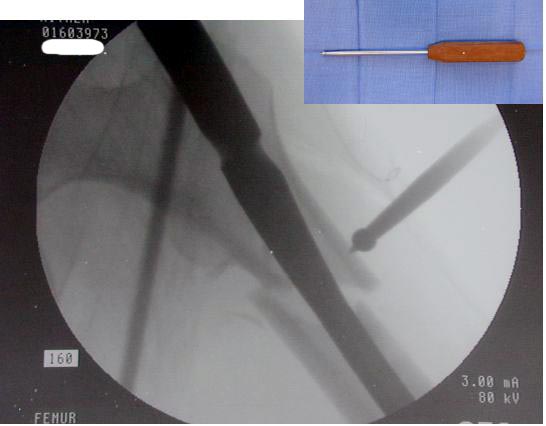

Большие преимущества у интрамедуллярных штифтов, метод хорош и можно произвести из минимального доступа, но во время операции необходимо контролирование варуса, затем приступить к блокированию.

Контролировать варус